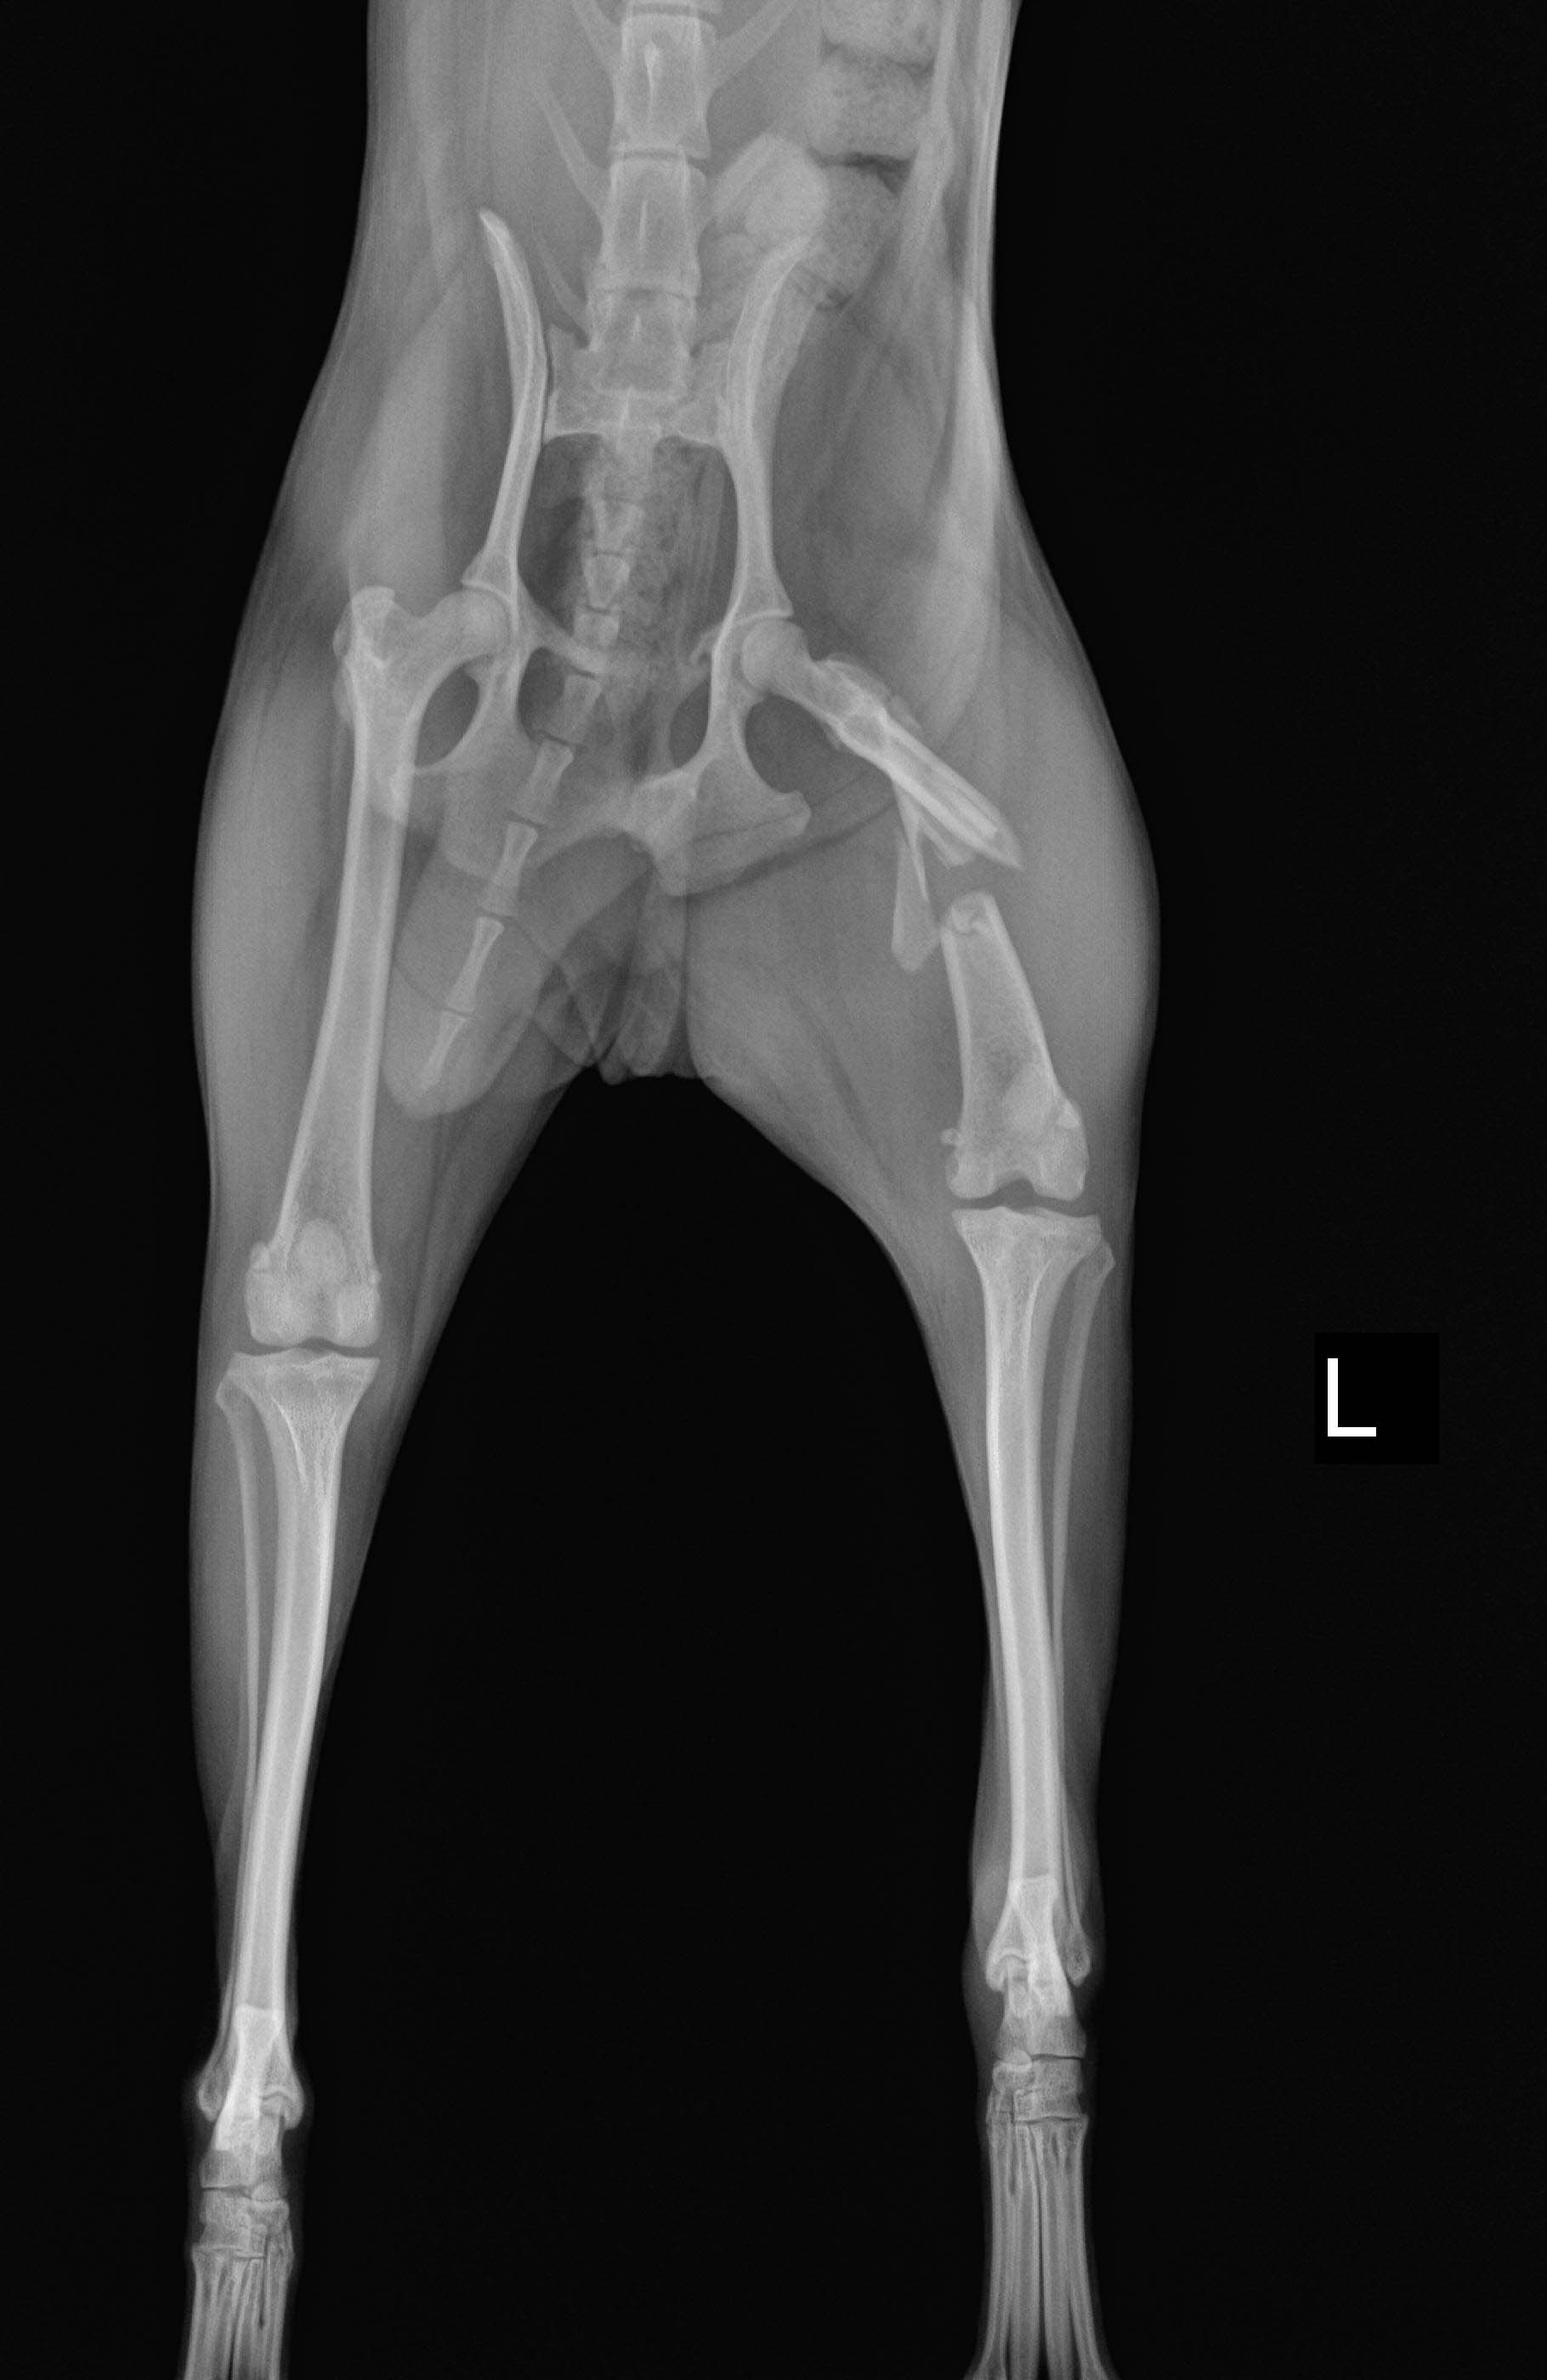

반려동물 질병 검사 과정에 필요한 엑스레이, 초음파 등의 영상을 기반으로 근골격계 질환 진단에 활용하는 AI 기술 개발을 위한 데이터

메타데이터 구조표 데이터 영역 영상이미지 데이터 유형 이미지 데이터 형식 jpg 데이터 출처 동물병원 라벨링 유형 바운딩박스/폴리곤/라인 라벨링 형식 JSON 데이터 활용 서비스 반려동물 질병진단 서비스 데이터 구축년도/

데이터 구축 규모 구분 구축량 질환데이터 정상데이터 질환비율 (건) (건) (건) (%) Mu01(골격계종양) 31,597 170 31,427 0.50% Mu02(사지골절) 27,141 1,323 25,818 4.90% Mu03(갈비뼈골절) 44,071 763 43,308 1.70% Mu04(엉덩관절탈구) 11,059 1,072 9,987 9.70% Mu05(슬개골탈구) 12,600 4,737 7,863 37.60% Mu06(전십자인대파열) 14,342 1,187 13,155 8.30% Mu07(추간판질환) 19,332 1,145 18,187 5.90% 합계 160,142 10,397 149,745 6.50% -

데이터 구성 항목 타입 필수 비고 유효값 / 허용범위 / 예시 유효값 설명 국문영 영문영 여부 Species 종별 string Y 종 (개 90%, 고양이 10% ) D, C 개(D), 고양이(C) 구분 Mission-id 과제 ID string Y 세부과제번호(복부, 흉부, 근골격계) 60, 61, 62 60 = 복부 61=흉부 62=근골격계 Birth 생년일 string Y 생년월일 ex) 20020829 형식 : YYYYMMDD Sex 성별 string Y 성별 (수컷, 암컷, 중성화수컷, 중성화암컷) IM, IF, CM, SF 형식 : Male(IM) / Female(IF) / Castrated male(CM) / Spayed female(SF) Hospital-id 병원 코드 string Y 원천데이터 제공병원코드 ex)0023, 0195 수집병원에 대해 일련번호를 정해 사용 (4자리) Disease 질환 유무 string Y 질환 유무 (정상 70%, 질환 30%) ABN, NOR 질환(ABN), 정상(NOR) Disease-Name 질환 부위-명 string Y 복부(Ab), 흉부(Ch), 근골격(Mu) 질환명분류:복부(10종),흉부(7종),근골격계(7종) Date 촬영 시간 string Y 촬영 시간/일자 ex) 20020829 Position 촬영 자세 string Y 촬영 자세 복부(60), 흉부(61) : VD, Lateral 근골격계(62):VD,Lateral,AP,ML Annotation-id 어노테이션 ID string Y 어노테이션 ID 11779877 어노테이션 포맷